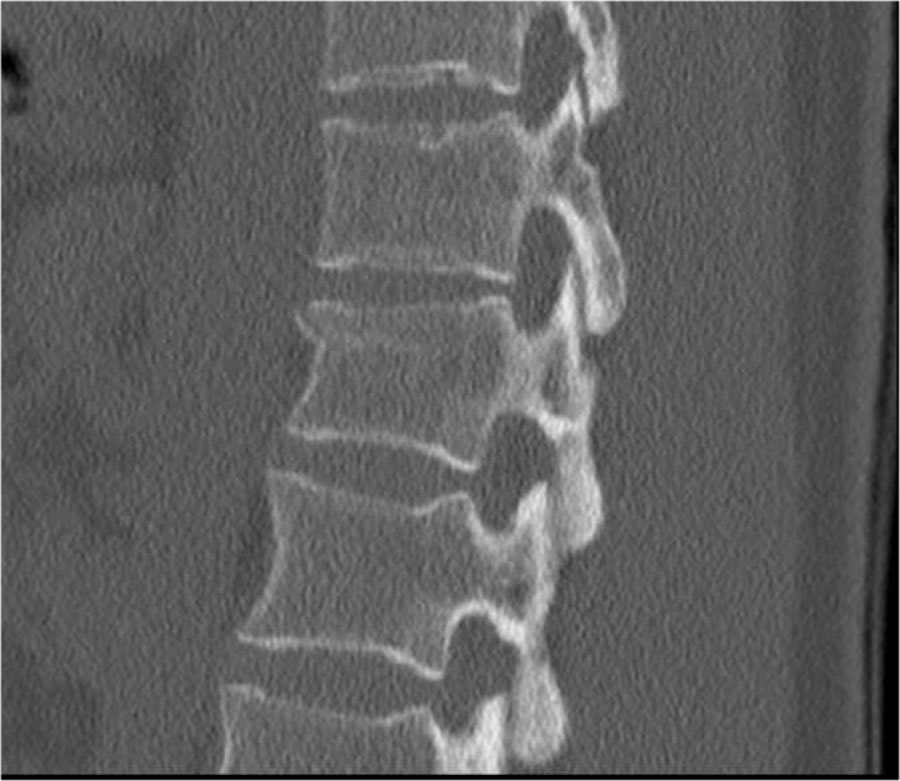

Gãy xương nén đơn thuần là dạng chấn thương phổ biến nhất, chiếm 90% các trường hợp.

Biểu hiện là mất chiều cao phần trước thân đốt sống hoặc tổn thương mâm sụn đốt sống.

Vỏ xương phía sau thân đốt sống phải còn nguyên vẹn — đây là đặc điểm phân biệt gãy nén đơn thuần với gãy vỡ (burst fracture) nặng hơn.

Vỏ xương phía sau có thể phồng nhẹ ra sau trong gãy nén đơn thuần. Miễn là không có mảnh xương tự do di lệch ra sau, tổn thương được phân loại là gãy nén hình nêm chứ không phải gãy vỡ.

Các hình ảnh cho thấy một trường hợp gãy xương nén.

Dấu hiệu duy nhất quan sát được là sự gián đoạn vỏ xương ở thành trước trên của thân đốt sống và mất chiều cao nhẹ ở phía trước.

Vỏ xương phía sau thân đốt sống còn nguyên vẹn.

Hình tái tạo mặt phẳng đứng dọc cũng cho thấy sự gián đoạn vỏ xương.